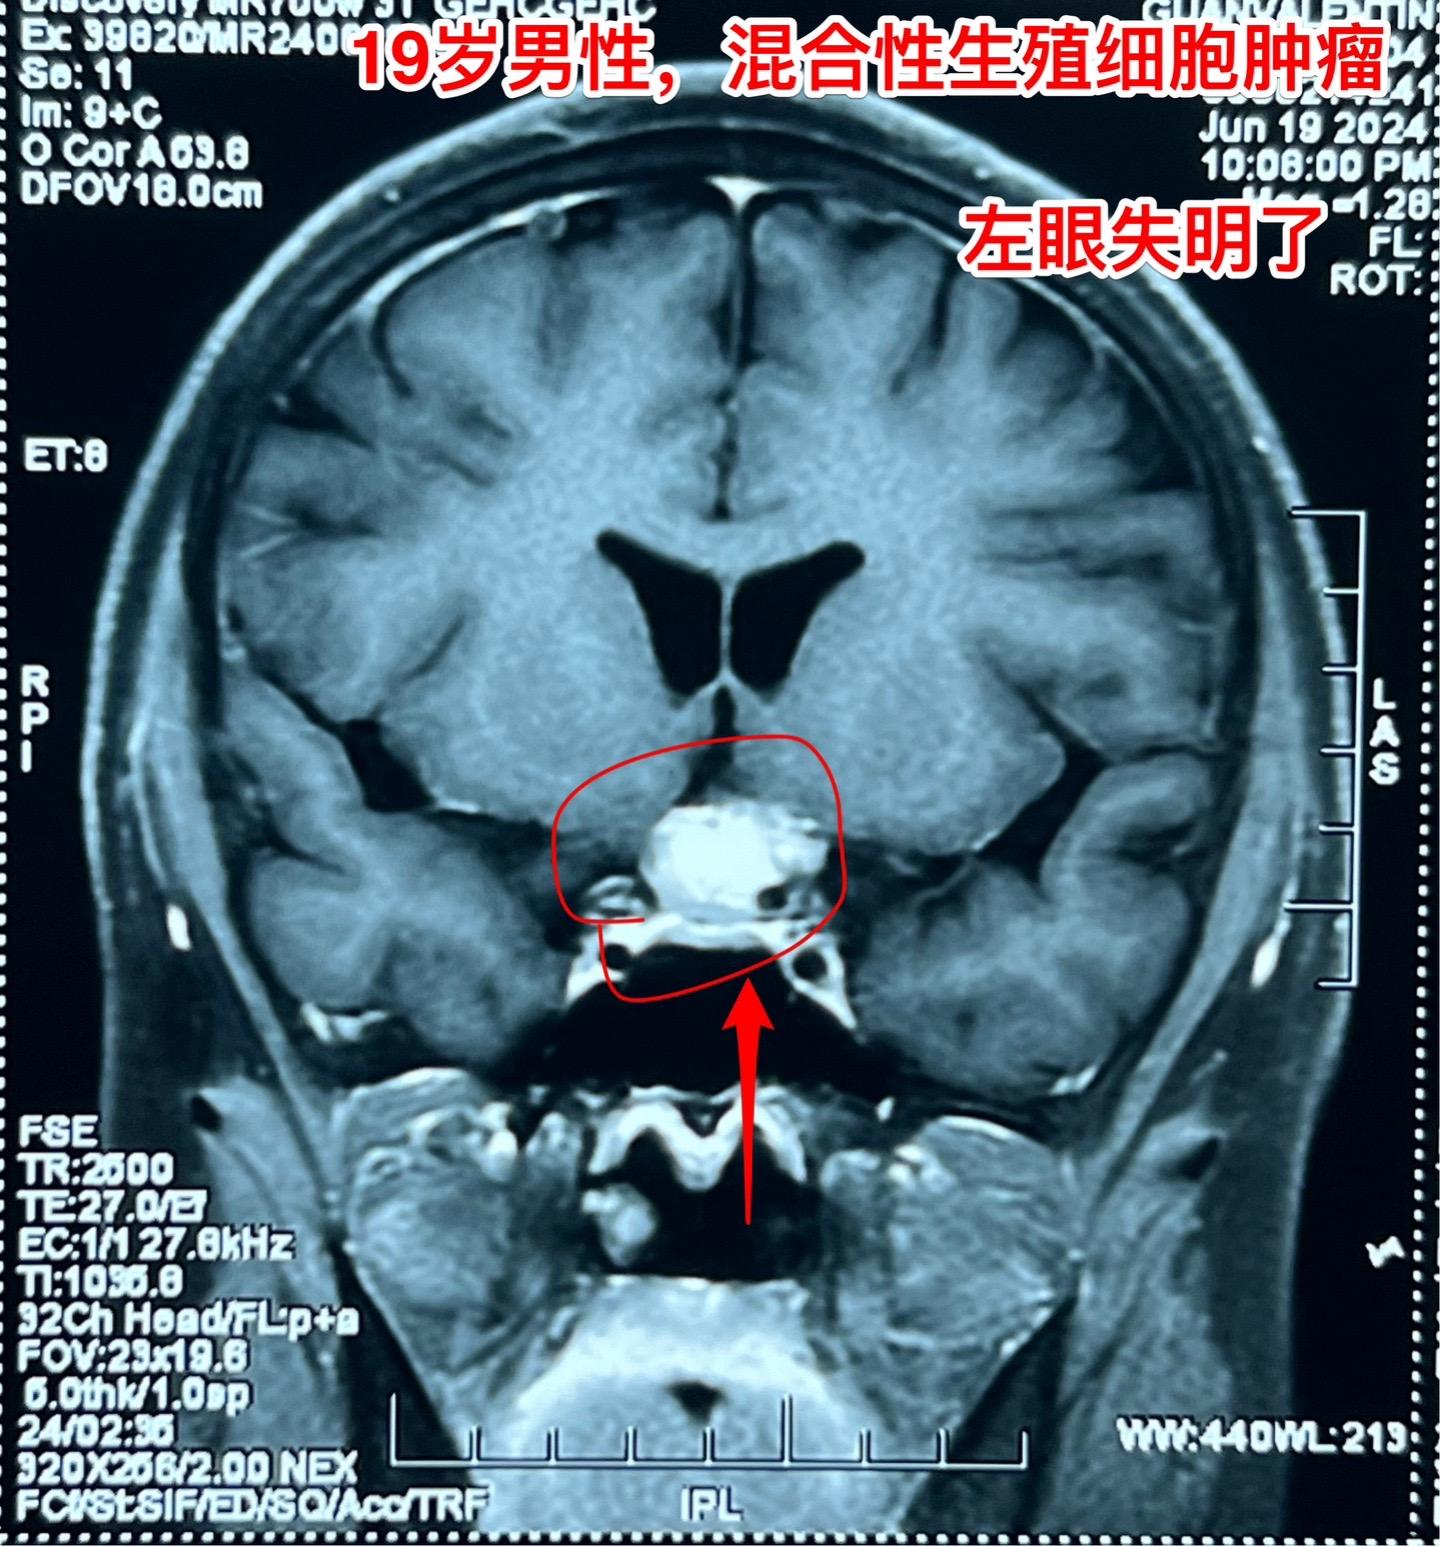

混合性生殖细胞肿瘤复发需要综合治疗。19岁莆田籍男性,三年半前还是新冠疫情期间,就因头痛发现松果体区肿瘤,怀疑是生殖细胞肿瘤,经过伽马刀治疗+化疗,肿瘤消失了,病人能正常上学。 2023年12月病人出现左眼视力下降,多饮多尿症状,复查磁共振显示鞍区肿瘤。取肿瘤活检提示是混合性生殖细胞肿瘤。化疗两个疗程,肿瘤体积稍微变小,停止化疗后肿瘤体积有增大,左眼视力呈恶化趋势,到北京三博来就医时左眼已经失明了。肿瘤的影像学资料见图。化验肿瘤标记物AFP、beta HCG均高于正常,这种情况下首选的是作